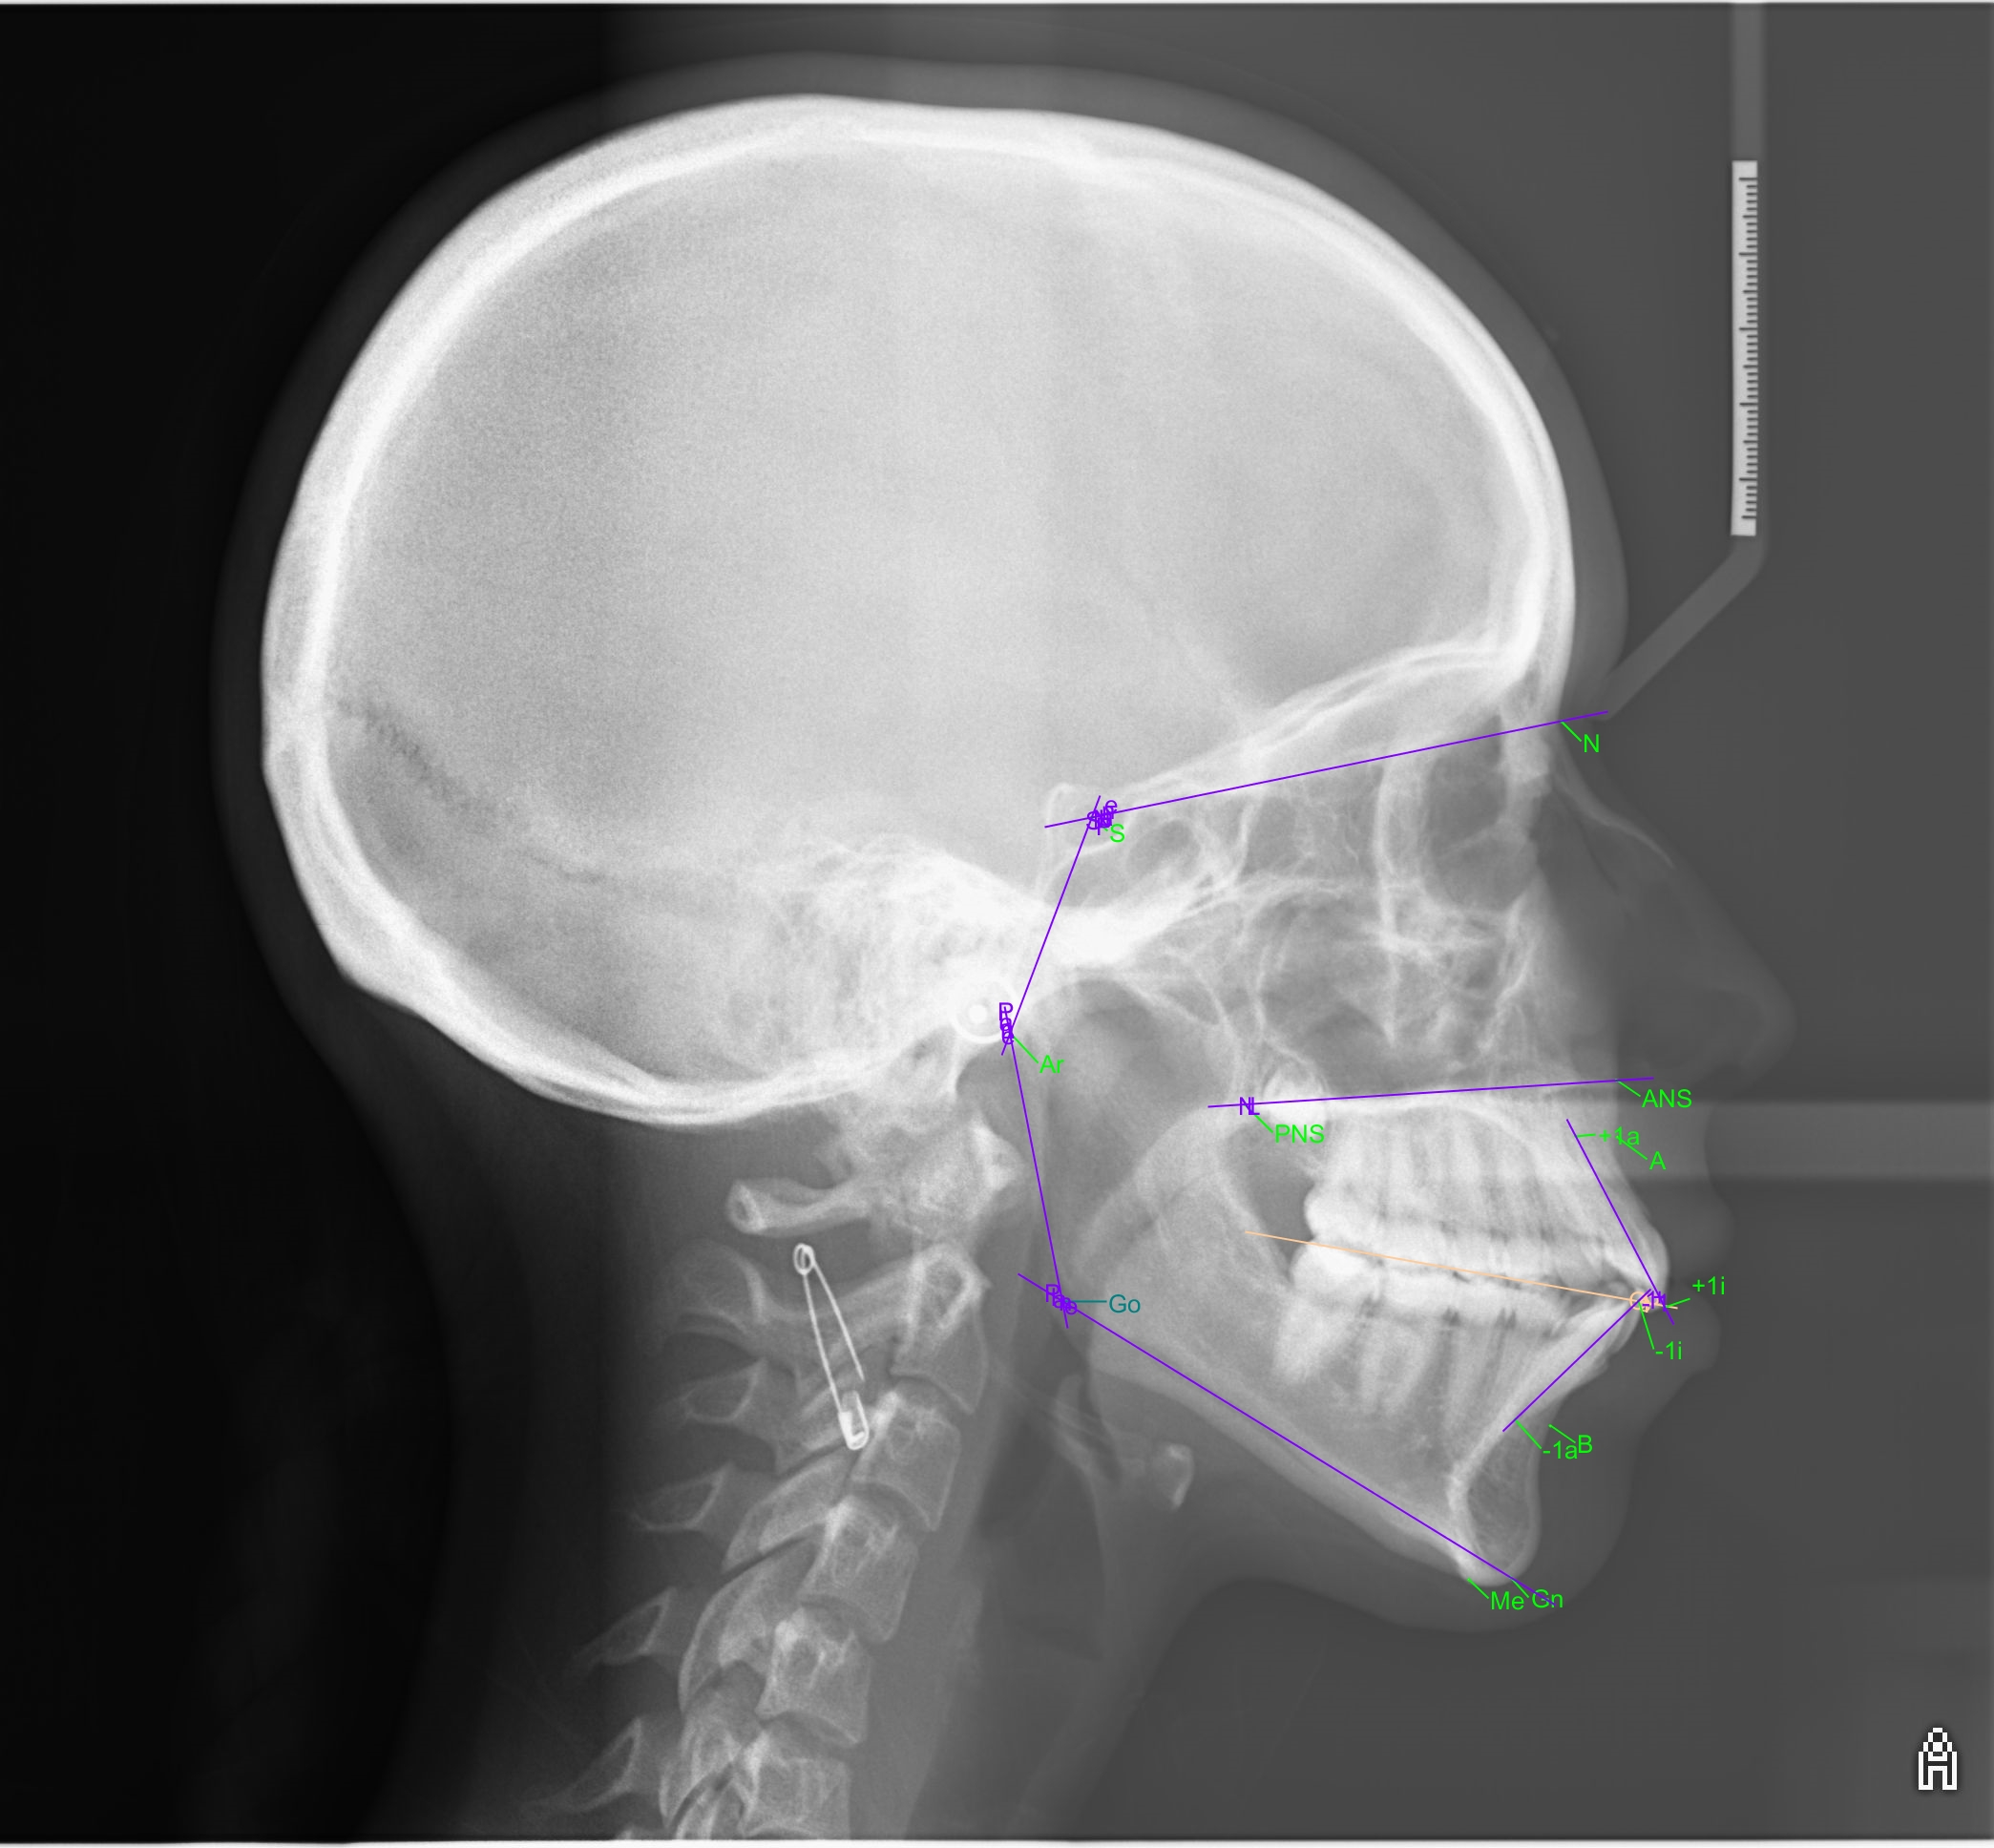

Spark™ treatment of teenager with moderate dento-maxillary discrepancy

This article describes a treatment with Spark Clear Aligners in a 14 year-old patient, with moderate DDM (Dento-Maxillary Disharmony), narrow arches, biproalveoli and hyperdivergence of the bony bases.

At the end of the treatment, which means only 8 months later, the control cephalometric analysis shows an improvement in the incisor axes despite the correction of a moderate DDM.

The Spark Aligners therefore enabled Dr. Pierre Antoine-Dian to obtain a good expansion of the arches, perfect torque control and resolution of the anterior crowding thanks to the protocols used and the predictability of the movements as well as the flexibility provided by Approver Software.